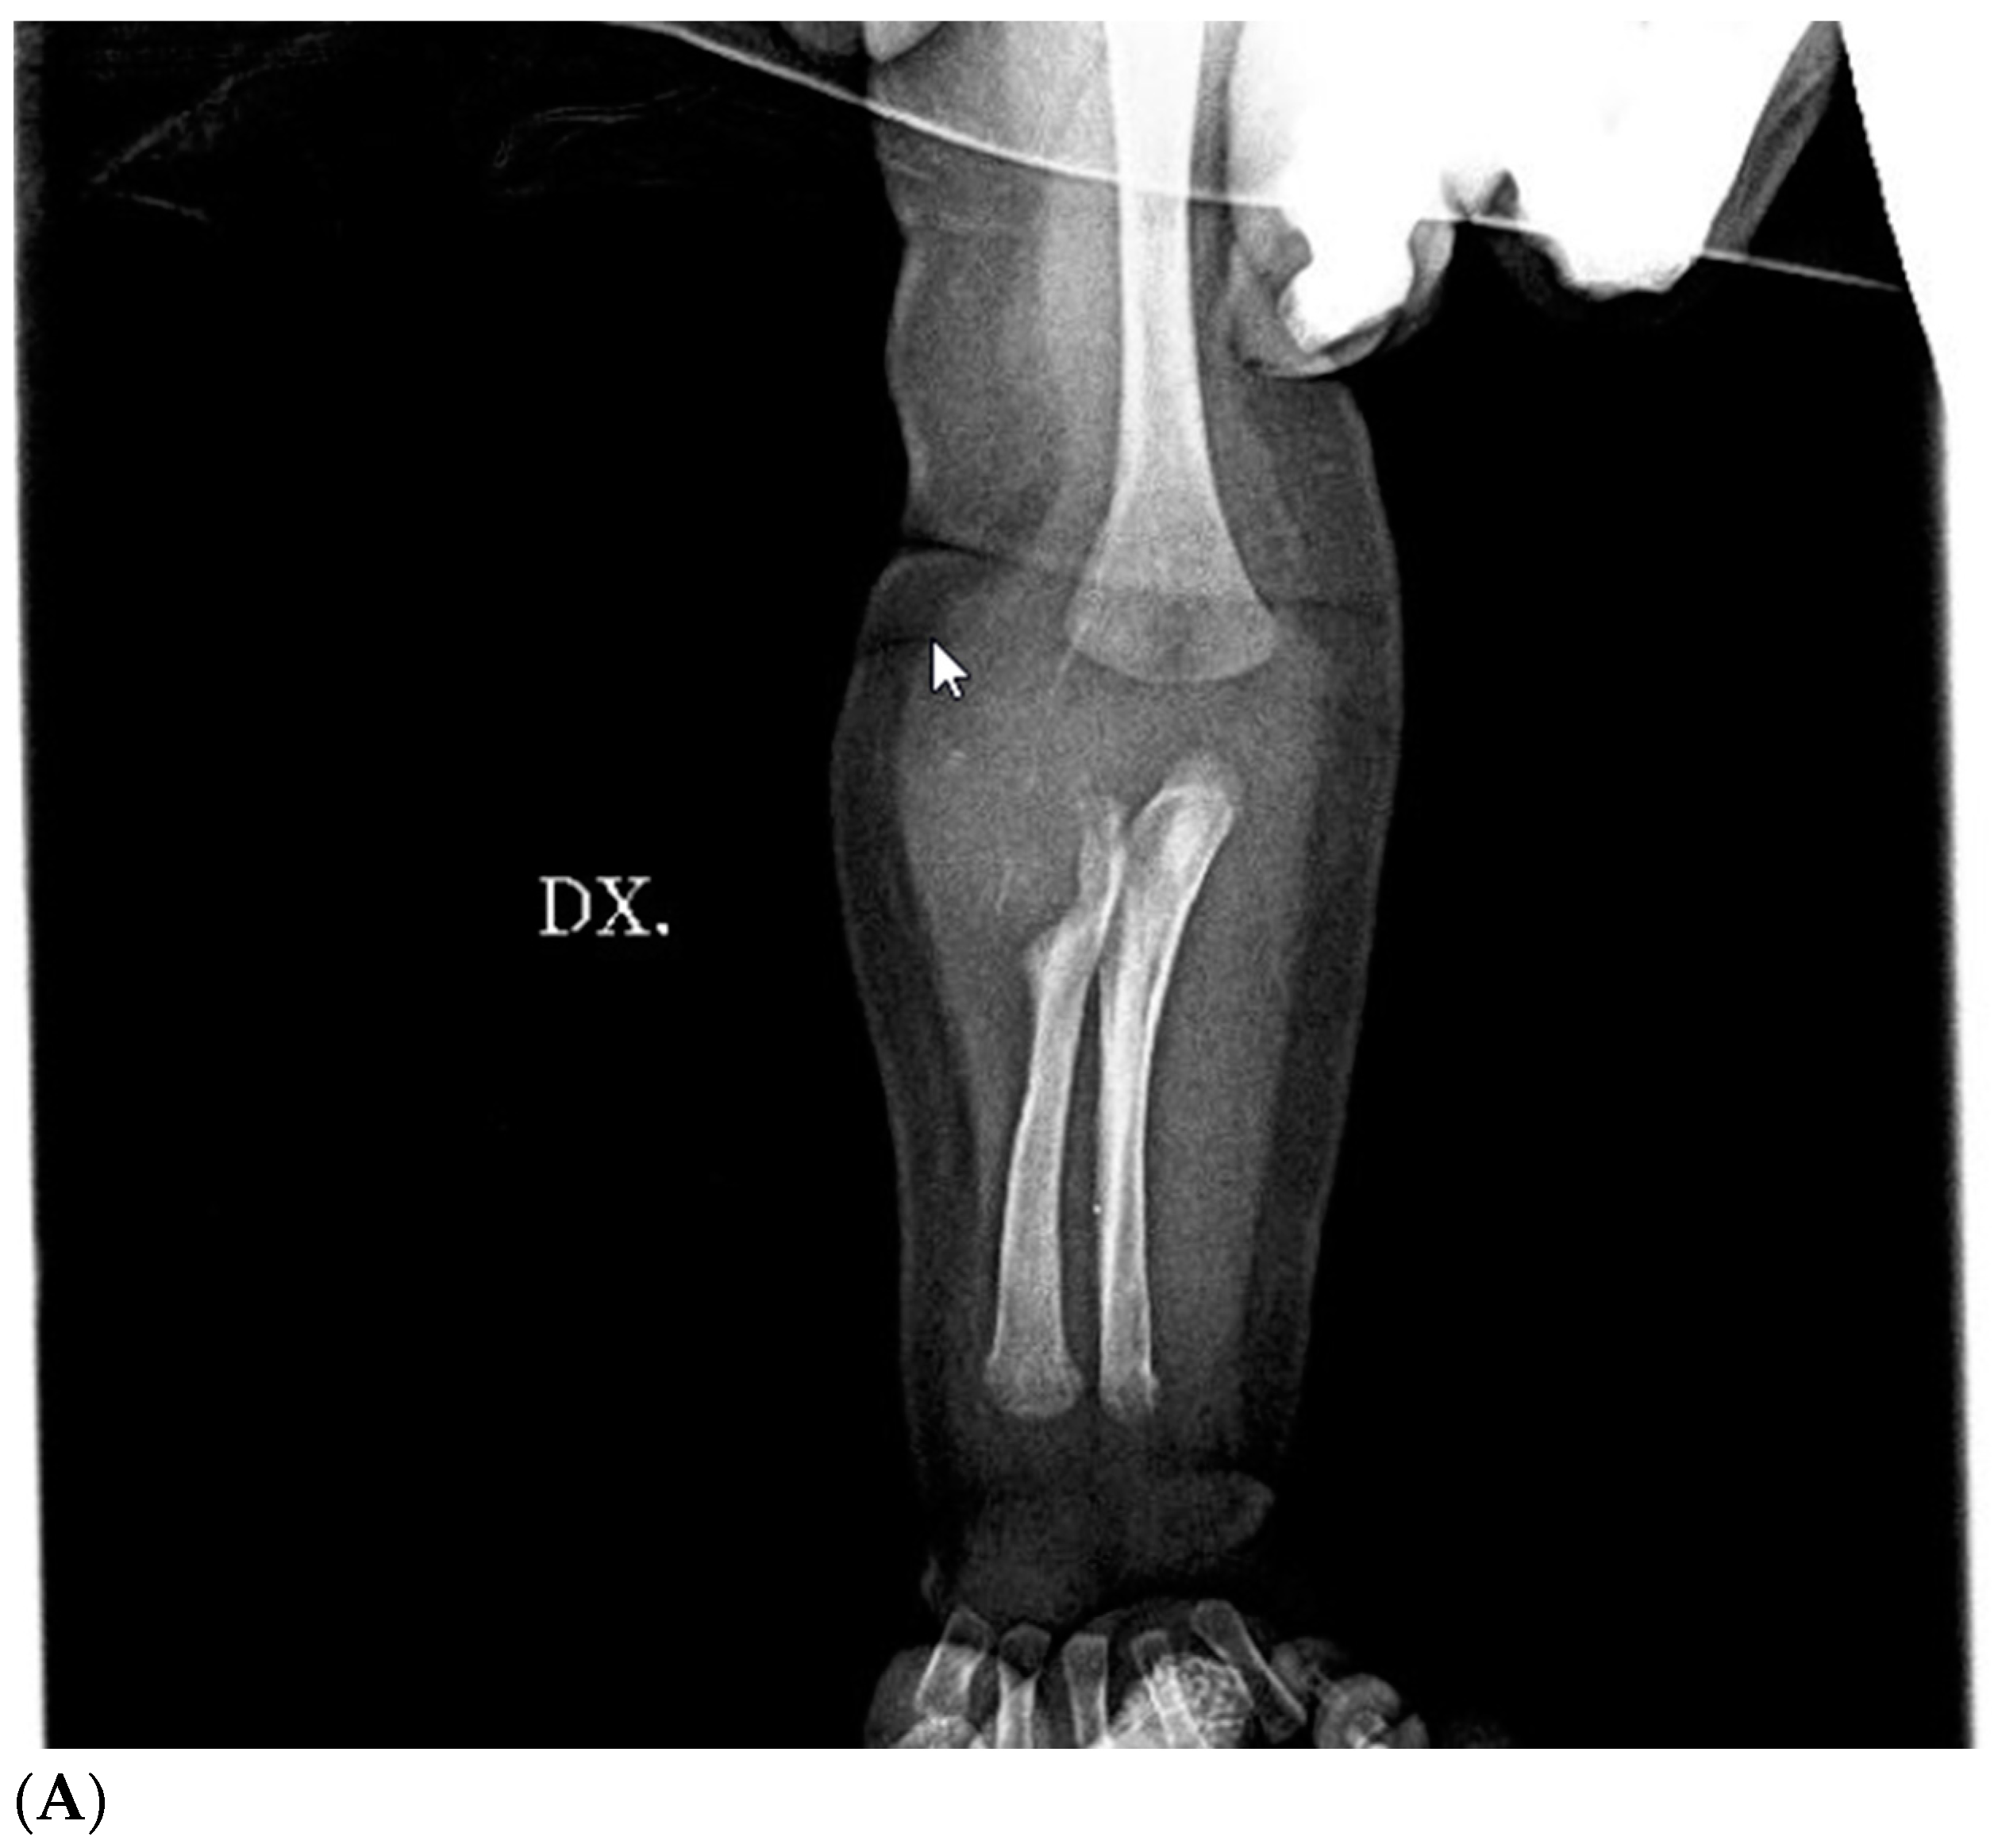

Figure 3.

Preoperative X-ray of right arm and forearm: large mass on the anterolateral surface of the right forearm near the elbow crease compressing (A) and eroding (B) the head of the right radio.